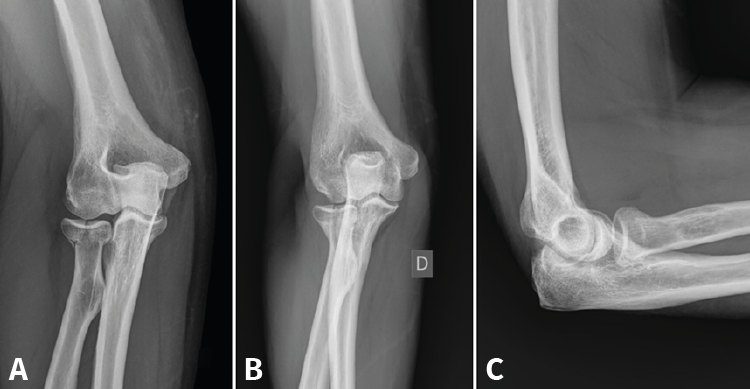

Las fracturas que afecten a menos de un tercio de la cabeza radial y que no produzcan bloqueo de la articulación podrían tratarse de igual modo que las de tipo I con buenos resultados a largo plazo. Inestabilidad y desplazamiento no son sinónimos. Incluso con un desplazamiento de más de 2 mm o con más de un fragmento, hay fracturas que siguen siendo estables gracias a que las estructuras periósticas están preservadas; por tanto, no son indicación absoluta de tratamiento quirúrgico (Figura 2)(11,12).

Figura 2. Ejemplo de fractura de Mason II tratada de forma conservadora. A: proyección anteroposterior (AP) aguda; B y C: AP y lateral a los 6 meses.